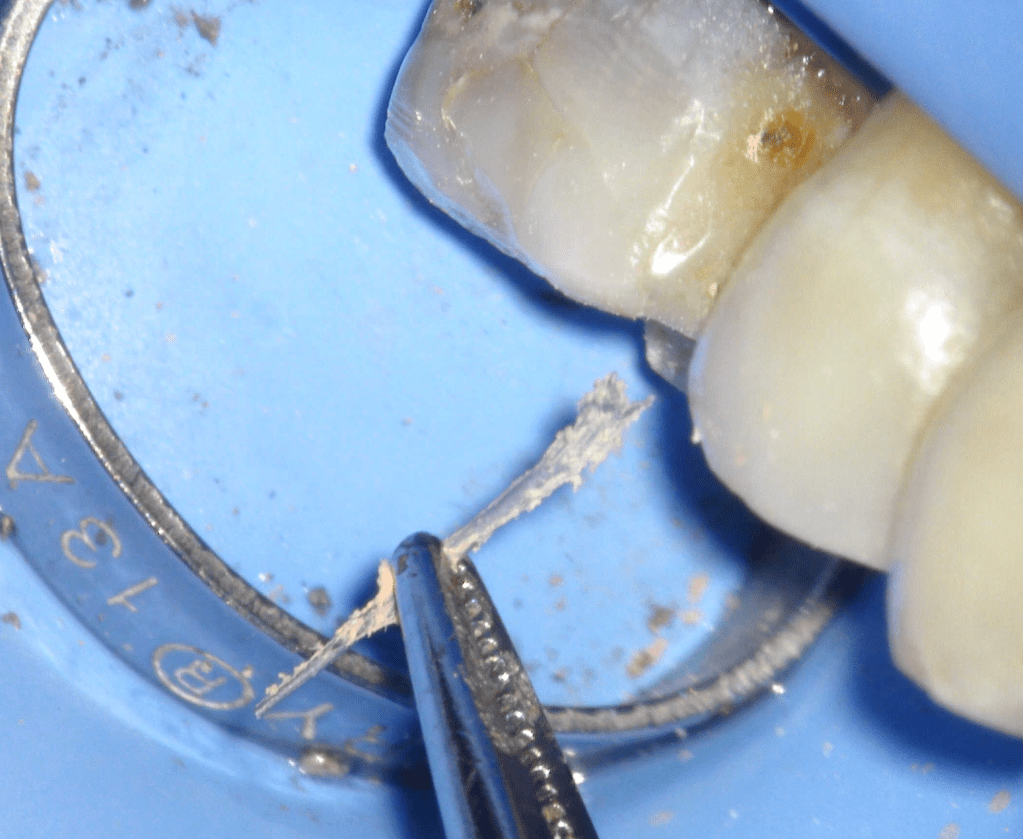

Fisura, remoción amalgama para explorar